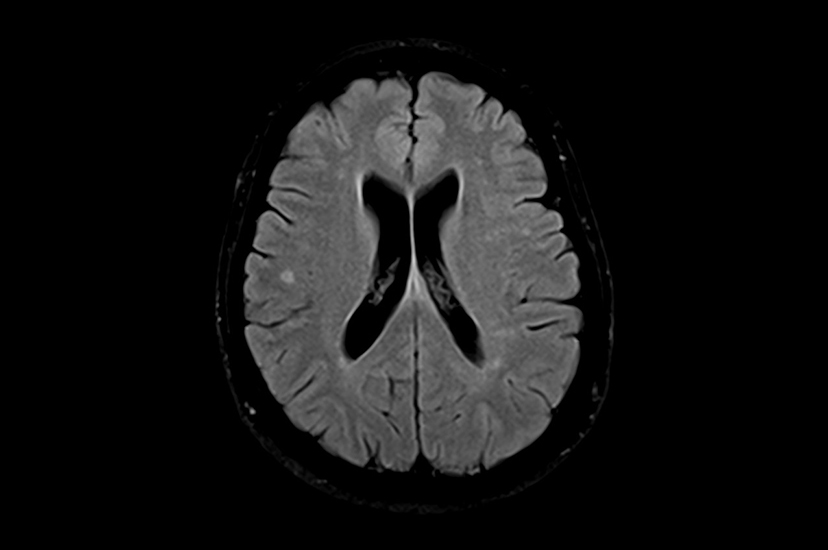

Хроническая ишемия головного мозга и лейкоареоз: симптомы и лечение